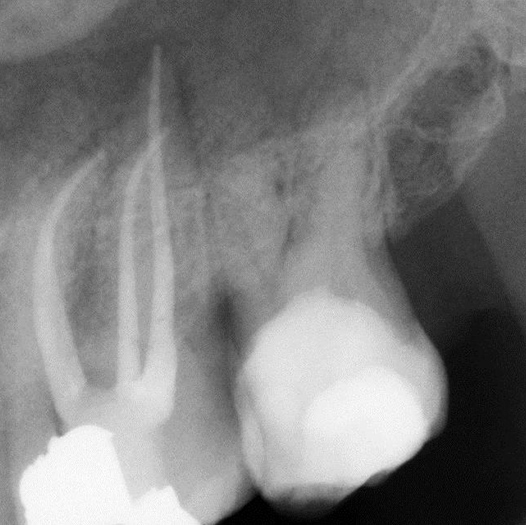

Before

Before Root Canal treatment